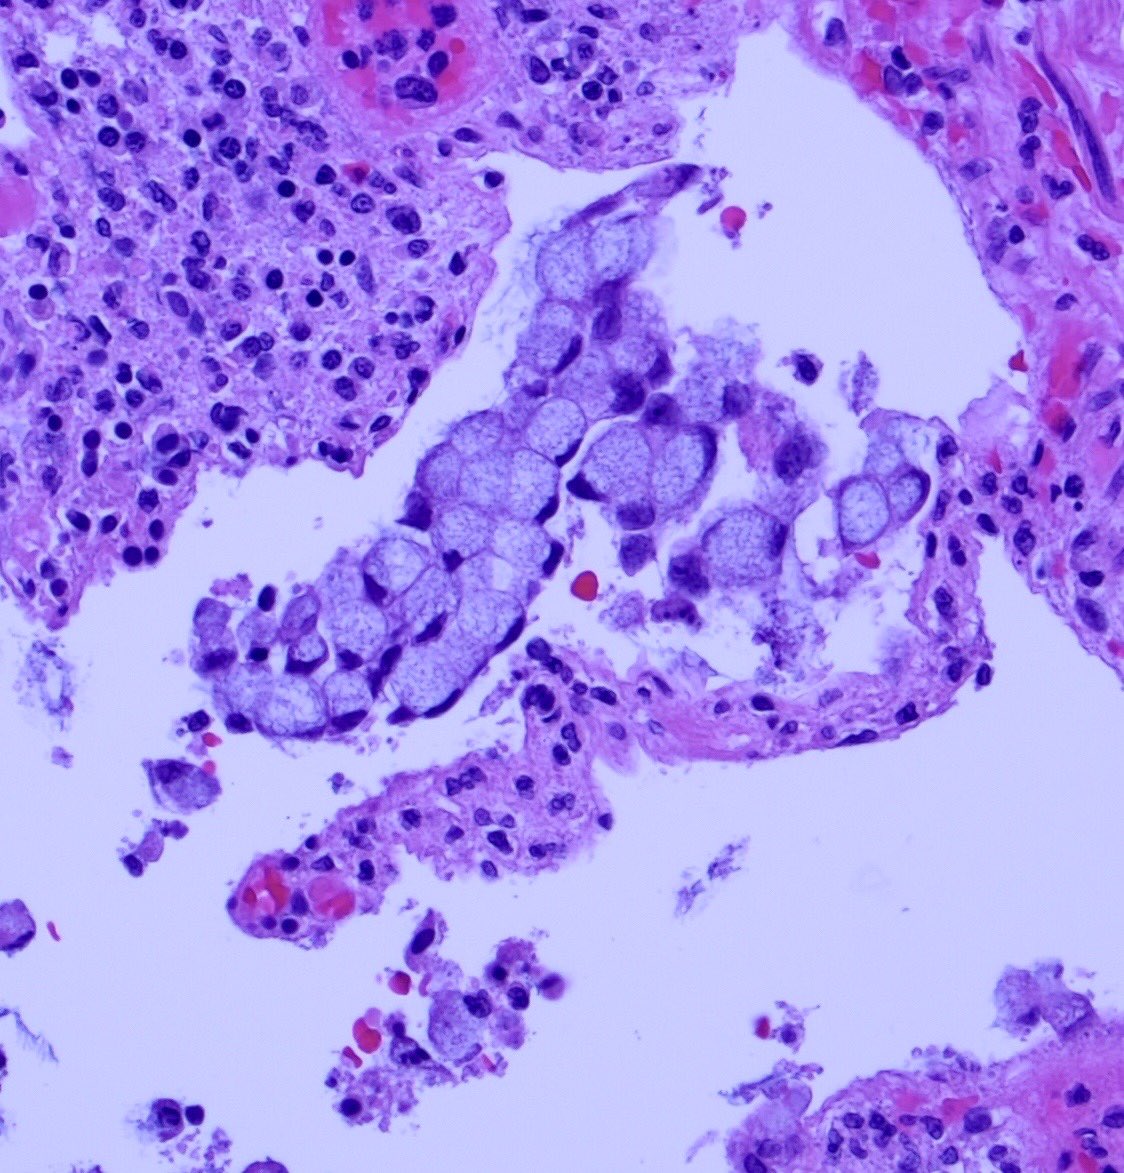

Some of these cells are showing classic ‘signet ring’ morphology:

How do we differentiate benign signet ring cell change from signet ring adenocarcinoma?

Context is key: signet ring cell change may be seen in pseudomembranous colitis; also other ischemic and ulcerative conditions.

The cause of signet ring cell change isn’t completely understood. Apparently, mucosal inflammation and ischemia cause epithelial cells to slough and ‘round up’, resulting in signet ring-like morphology.